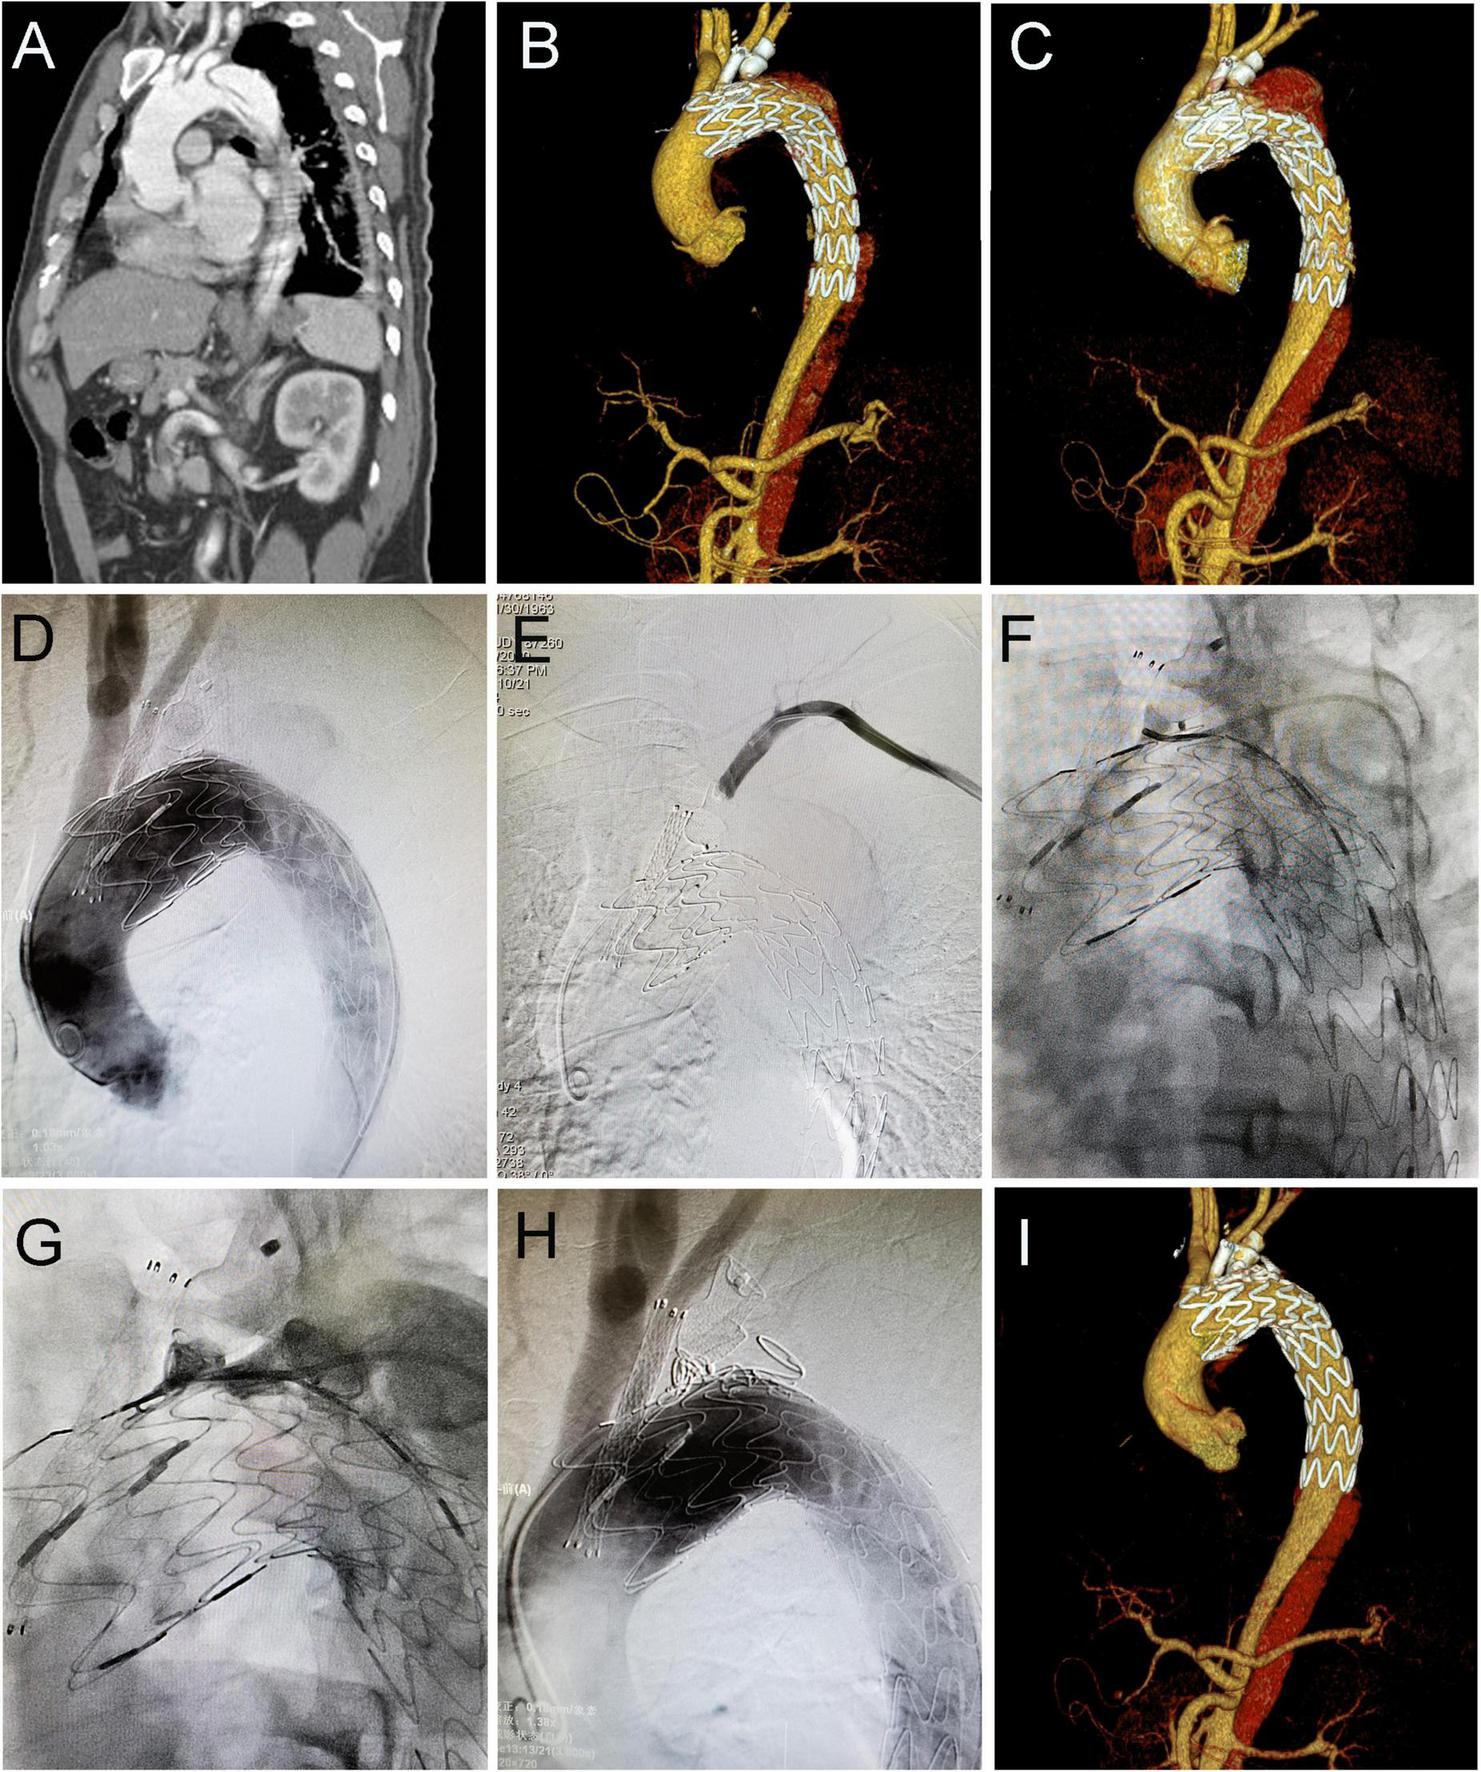

During follow-up, the type IA endoleak disappeared spontaneously in 14 patients, while three patients with progressively increased type IA endoleak received the secondary intervention (two with coil embolization and one with LSA chimney stent angioplasty). As shown in Figure 2, the patient underwent TEVAR with a chimney stent deployed in LCCA and duct occluder in LSA. He showed progressed type IA endoleak after TEVAR and received coil embolization 4 years later, and then the endoleak totally resolved. The remaining 16 patients with persistent type IA endoleak continued to be monitored with close surveillance. Thus, the rate of persistent and re-intervened type IA endoleak was 5.5% (19/345). Type II endoleak from LSA disappeared spontaneously in two patients, two patients with progressed type II endoleak were re-intervened (one with duct occluder and the other with one more stent deployed in LSA and angioplasty). The rest of the two patients with persistent type II endoleak continued to be managed with conservative treatment.

FIGURE 2

Coil embolization for type IA endoleak 4 years after cTEVAR. Preoperative computed tomography angiography (CTA) showed aortic dissection involving the arch (A). The patient underwent cTEVAR with a chimney stent implanted in LCCA and duct occluder implanted in LSA, and postoperative CTA showed a type IA endoleak (B). The follow-up CTA 4 years later showed the endoleak was significant enlarged (C). With the catheter located in ascending aorta, an angiogram showed contrast could enter the false lumen (D). With the catheter located in LSA, the angiogram showed no contrast entering false lumen (E). With the catheter located in the false lumen, an angiogram showed contrast could enter the aorta (F). After deployment of coils in the false lumen, an angiogram showed contrast could not enter the aorta (G). Post-intervention angiogram (H) and CTA (I) showed the endoleak completely disappeared. cTEVAR, TEVAR with chimney; CTA, computed tomography angiography; LCCA, left common carotid artery; LSA, left subclavian artery; aRSA, aberrant right subclavian artery.